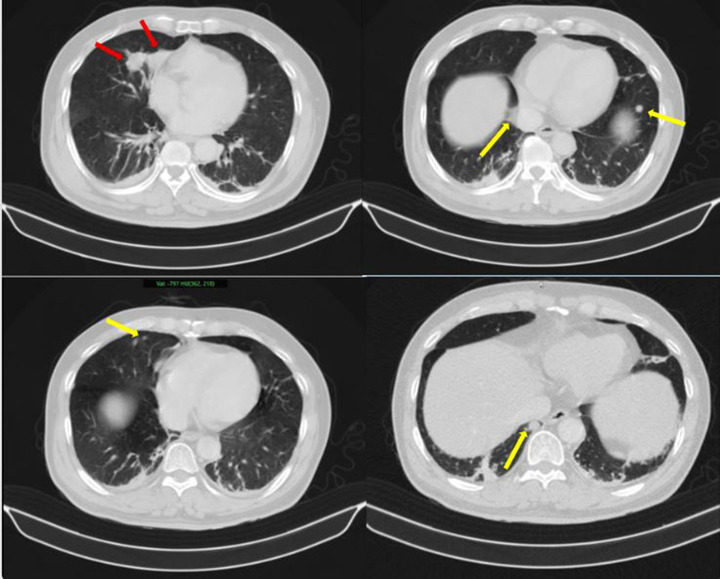

Người đàn ông phát hiện mắc hai bệnh ung thư cùng lúc- Ảnh 1.

Những hình ảnh bất thường trên phổi của bệnh nhân (Ảnh: BV Bạch Mai)